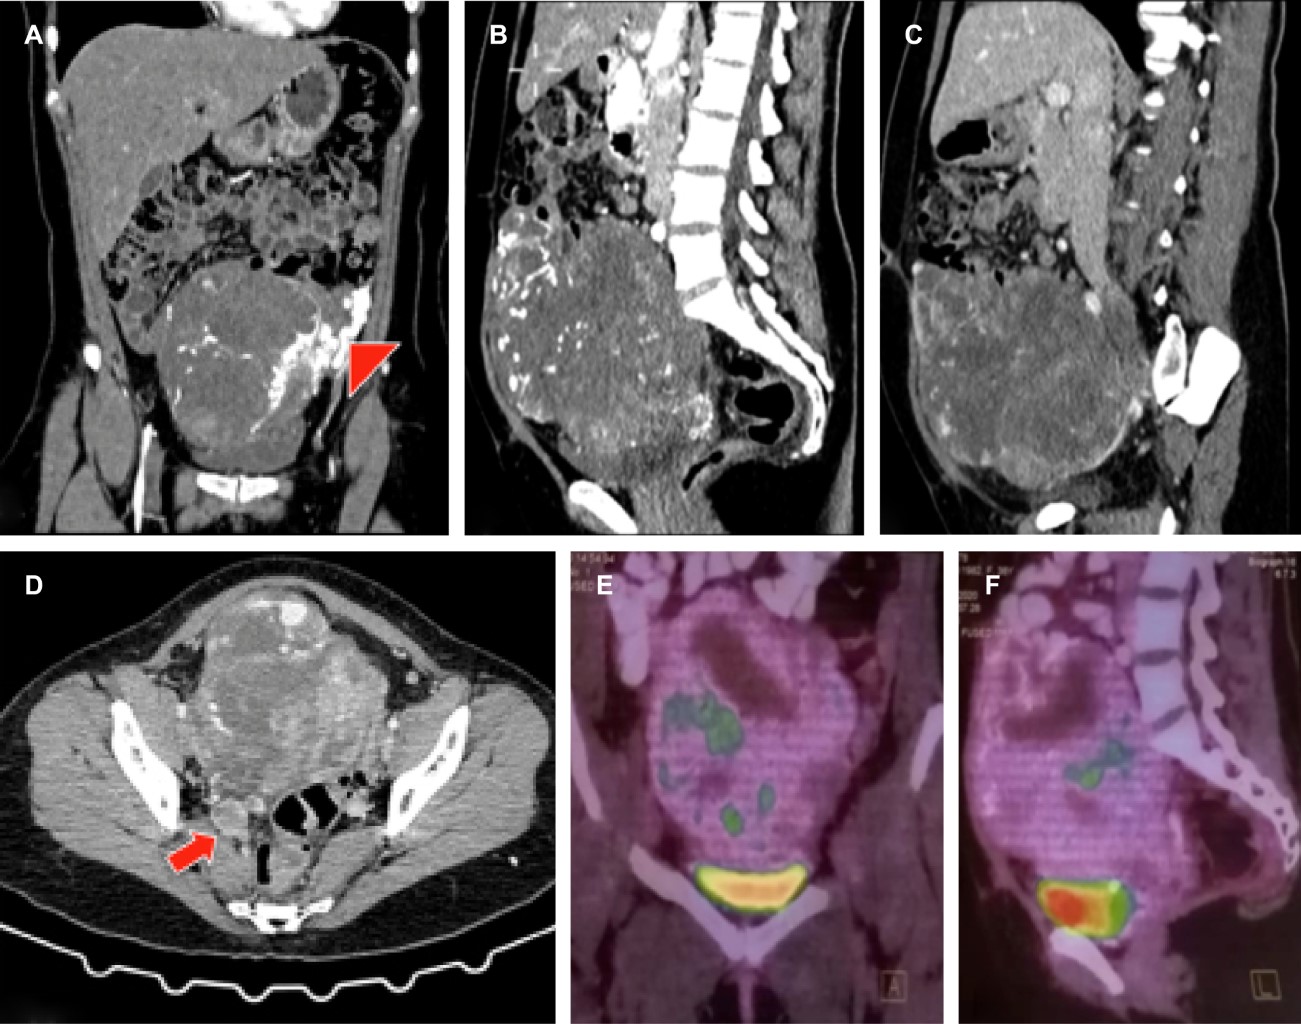

Se realiza angiotomografía toracoabdominal complementaria para valorar extensión neoplásica, que además de corroborar los hallazgos de resonancia magnética, evidencia finas calcificaciones tumorales, tinción tumoral arterial miometrial con shunts arteriovenosos que condicionan drenaje venoso anómalo temprano hacia la vena ovárica izquierda, la cual persiste dilatada con un calibre máximo de 13 mm hasta su desembocadura en la vena renal izquierda. Trombosis tumoral de la vena iliaca interna derecha con un calibre máximo de 26 mm, que se extiende hacia la desembocadura de la vena cava inferior (Figura 3). Uréteres dilatados con desplazamiento lateral, sin datos de hidronefrosis asociada.

Nódulo pulmonar del segmento basal posterior del pulmón derecho adherido a la pleura, sin engrosamiento de ésta, con un diámetro de 9 mm, sin proyecciones estelares con valores de atenuación subsólidos.

Por el hallazgo del nódulo pulmonar, se decide realizar como complemento PET-CT de cuerpo entero con 18-FDG que corrobora el tumor dependiente del útero, de densidad heterogénea, con zonas hipodensas e hipometabólicas, con relación a necrosis. Se asocia a incremento anormal del metabolismo de forma irregular y heterogénea con SUV máximo de 5.26 que en fase tardía disminuye su metabolismo hasta SUV máximo de 4.98. El comportamiento metabólico sugiere neoplasia de bajo grado (Figura 3). Nódulo pulmonar se reporta sin metabolismo.

La angiotomografía ofrece información muy valiosa respecto a las calcificaciones tumorales y al comportamiento vascular intrínseco de la neoplasia, así como el entorno pélvico vascular arterial y venoso que determina en gran medida la planeación quirúrgica.

Las características moleculares en el estudio de PET-CT orientaron a una neoplasia de bajo grado, pero resaltó el hecho de que no fue compatible con el hallazgo histopatológico de alto grado, aunque el radioisótopo utilizado 18-FDG es genérico. De igual manera, el nódulo pulmonar se reportó sin metabolismo, dato relevante para la decisión quirúrgica. Es un estudio que no debe evitarse, sobre todo en la evaluación de enfermedad tumoral pélvica y a distancia principalmente.

Figura 3